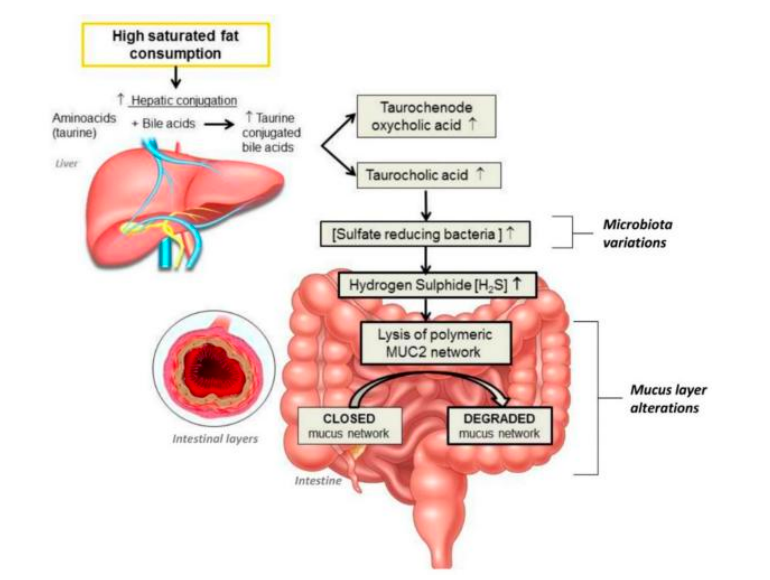

È ormai noto che la nutrizione svolga un ruolo importante nella patogenesi della malattia di

I batteri che abitano l’intestino umano sono strutturati come un ecosistema complesso che viene continuamente

Il microbiota intestinale è un ecosistema mutevole e continuamente modellato da fattori come ambiente, stile